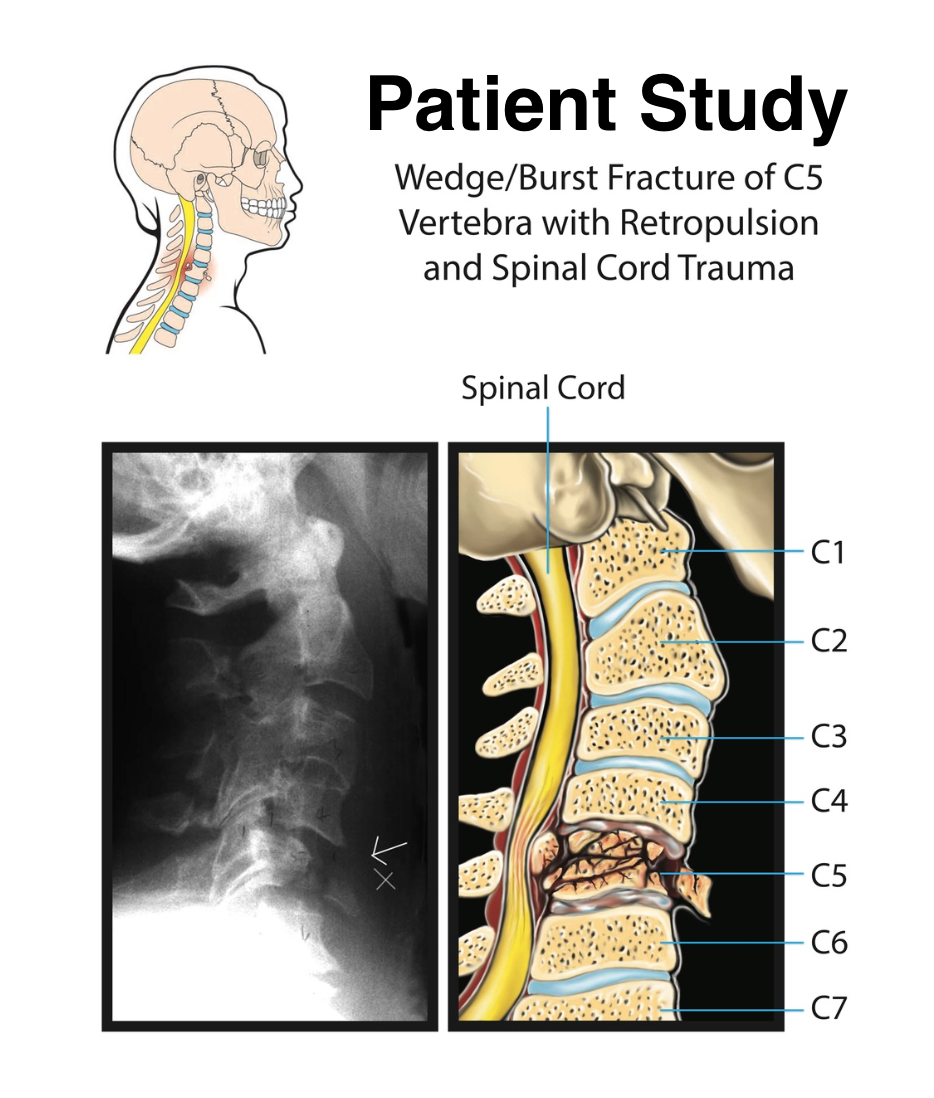

Biomedical art is a form of biological illustration that helps record and disseminate medical, anatomical, and related knowledge. It translates complex technical medical information into visual artwork to support research, patient care and education, public relations, and marketing objectives.